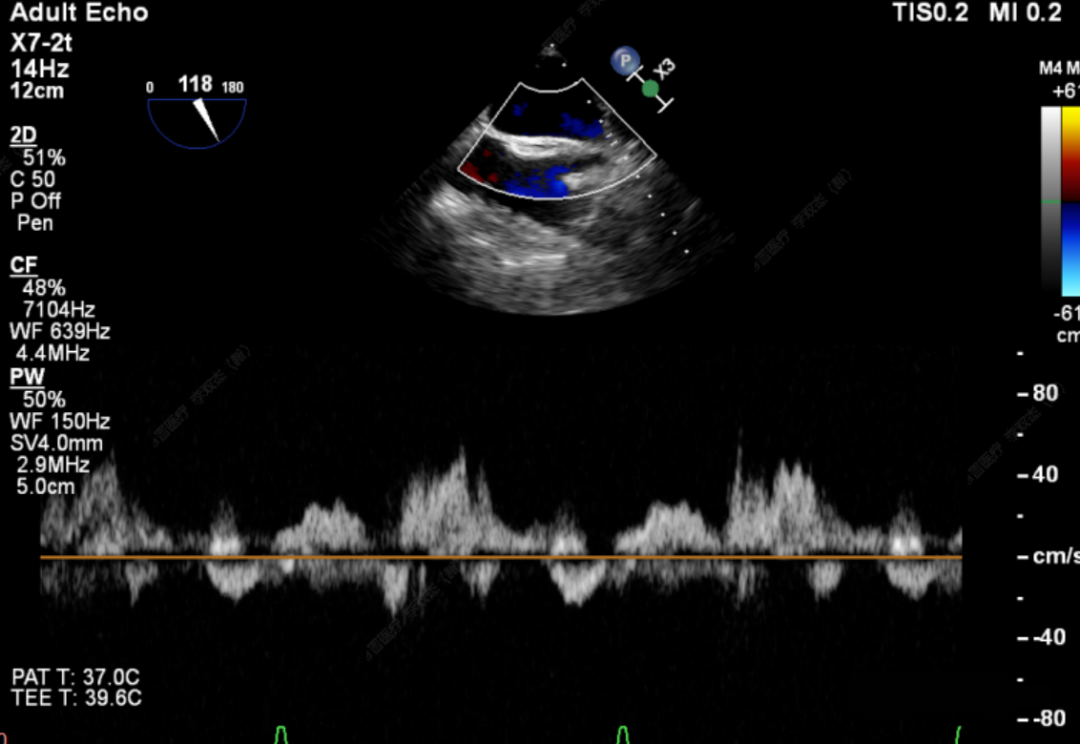

此次手术患者均为高龄、且外科高危的器质性二尖瓣反流,反流病变区域遍及前后瓣叶(一区、二区、三区),复杂及多样性的病变状况大大增加了手术的操作难度性,是对术者与器械稳定及有效性的巨大考验。术中,器械经股静脉穿刺房间隔,通过输送系统送入患者左心房,到达二尖瓣膜反流处,在经食道超声及DSA引导下,通过反复评估脱垂范围、抓捕位置、反流程度,确保细致操作、精准夹合、释放。术后即刻,患者反流显著减小,左房压下降,血流动力学改善明显,短暂过渡后,首位患者安返病房。导管室内,华西心脏瓣膜团队仍严阵以待,为之后两例手术做准备,经过团队之间紧密配合,三台手术均顺利完成。